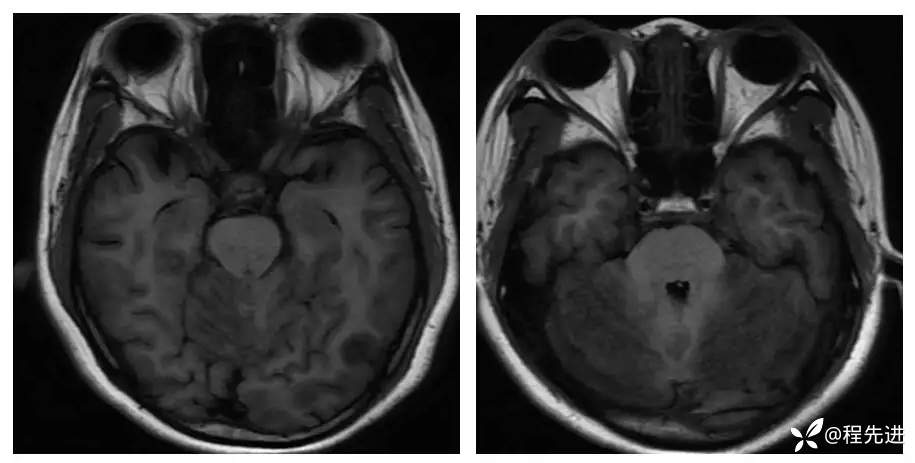

【现病史及既往史】:孕期38周,蛋白尿10天,血压升高6天,剖腹产后一天出现头晕,头痛,嗜睡。既往糖尿病史

查体:不配合,血压波动,130-157/85-109mmHg

影像检查: